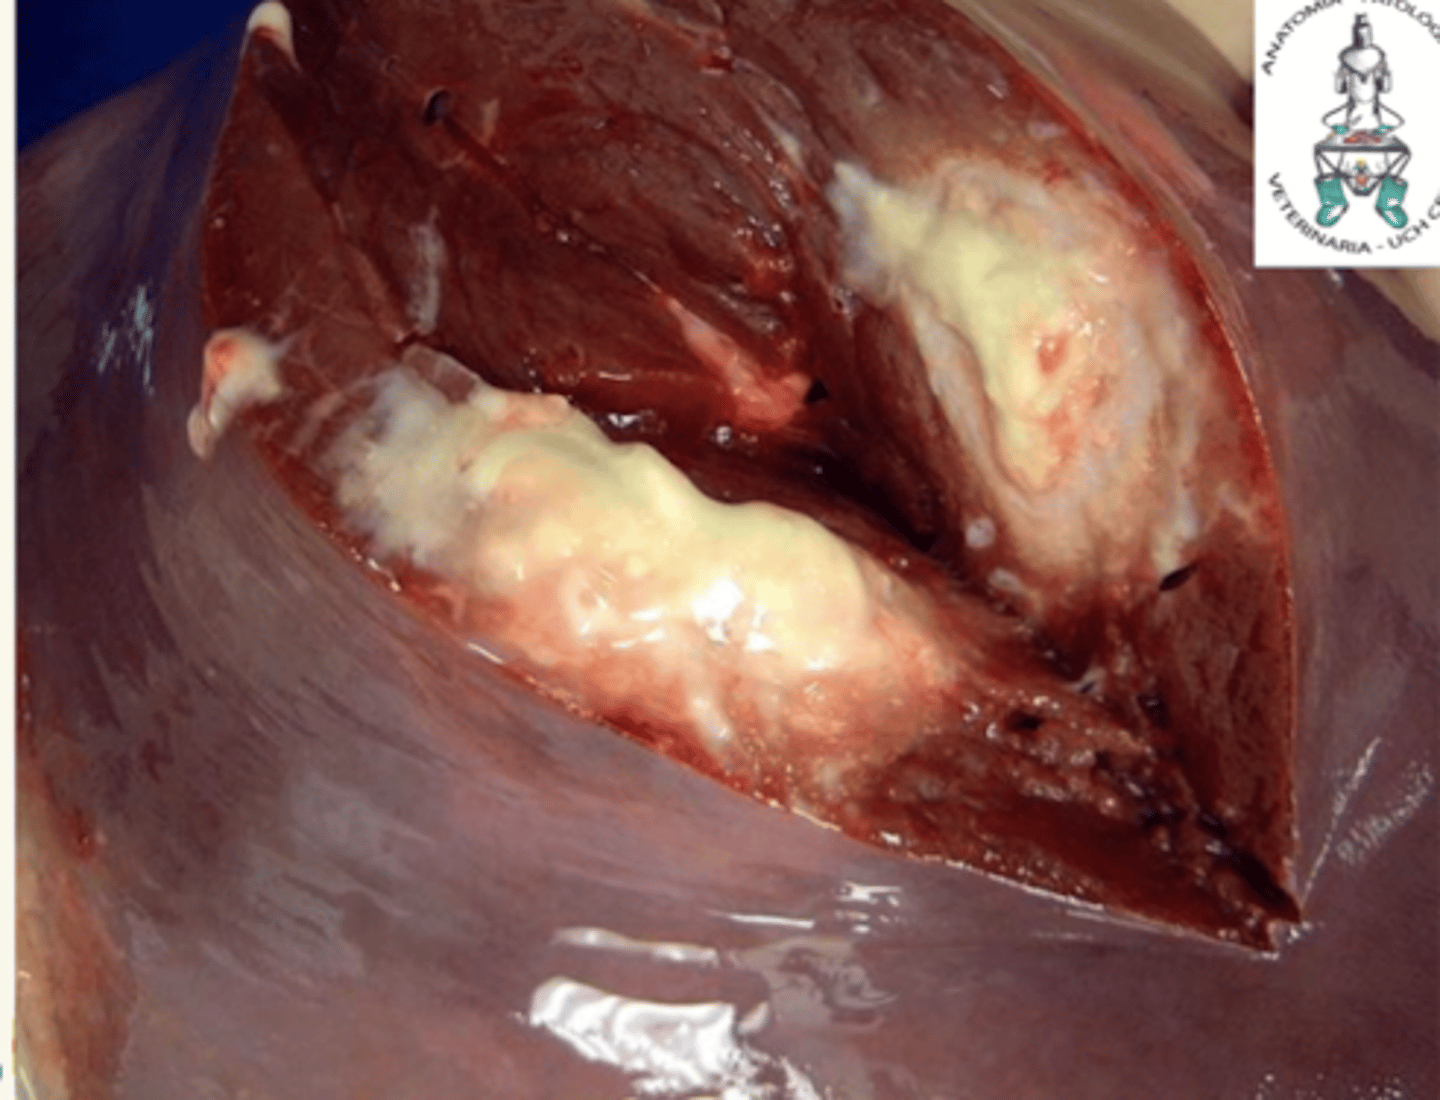

hepatitis necrotizante, por herpesvirus

¿diagnóstico morfológico y etiológico?

(cuerpos de inclusión intranucleares acidófilos)

hígado.